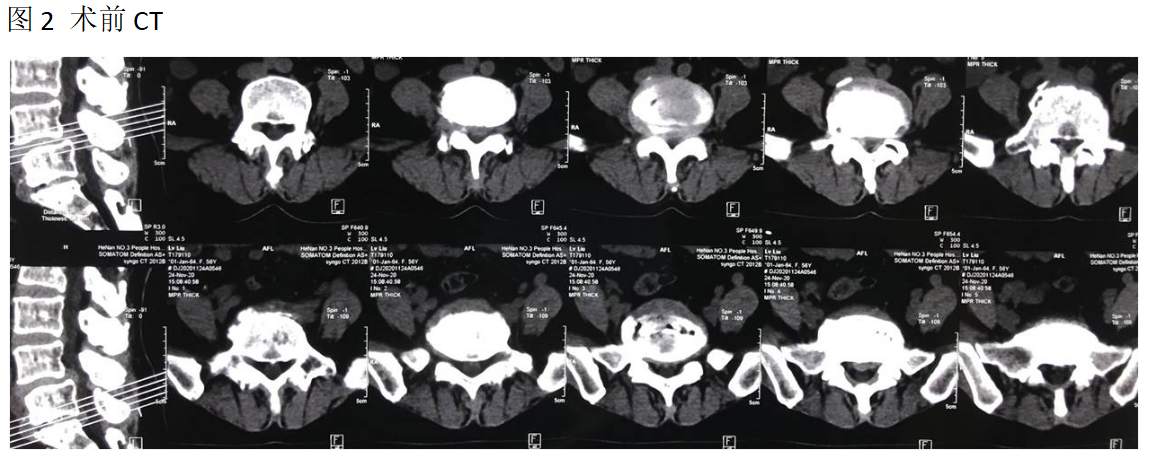

吕X,女,56岁。

主诉:腰疼及双下肢疼痛麻木伴活动受限3年加重半年。

查体:L4-5棘间及椎旁压痛,右下肢直腿抬高试验60°阳性,左下肢50°阳性,双下肢肌力肌张力正常。